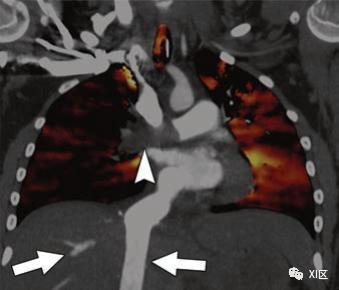

虽然在胸片上可以认为巨大的PAVM是一个突出的曲线结构,但许多PAVM最初被怀疑是因为在对已知或疑似HHT的患者进行超声心动图筛查时,由于其他原因无法解释从右向左分流。通过肺CTA确定AVM的位置、数量和大小,以预测治疗。通过小剂量测试或监测触发来优化肺动脉系统的强化水平。

在肺CTA上,PAVMs表现为增强的囊或扩张的血管团块。诊断需要有供血动脉和引流静脉,多平面MIP图像可提高对其的检测能力(图3)。如果可以的话,双能量扫描可以提供一个虚拟平扫序列,以排除疑似PAVM的钙化结节。

供血动脉的直径应在动静脉交通的近端、实质分支的远端大约2-3厘米测量。动脉直径大于3毫米表明病变可能适合经导管栓塞(图3)。如果PAVM不符合栓塞术的条件,建议随访肺部CTA以监测其生长情况。在儿科人群中,理想的随访间隔并不是很明确,常见的随访间隔为1到10年。Ratjen等人在HHT患儿中发现PAVM的平均年增长率约为10%。